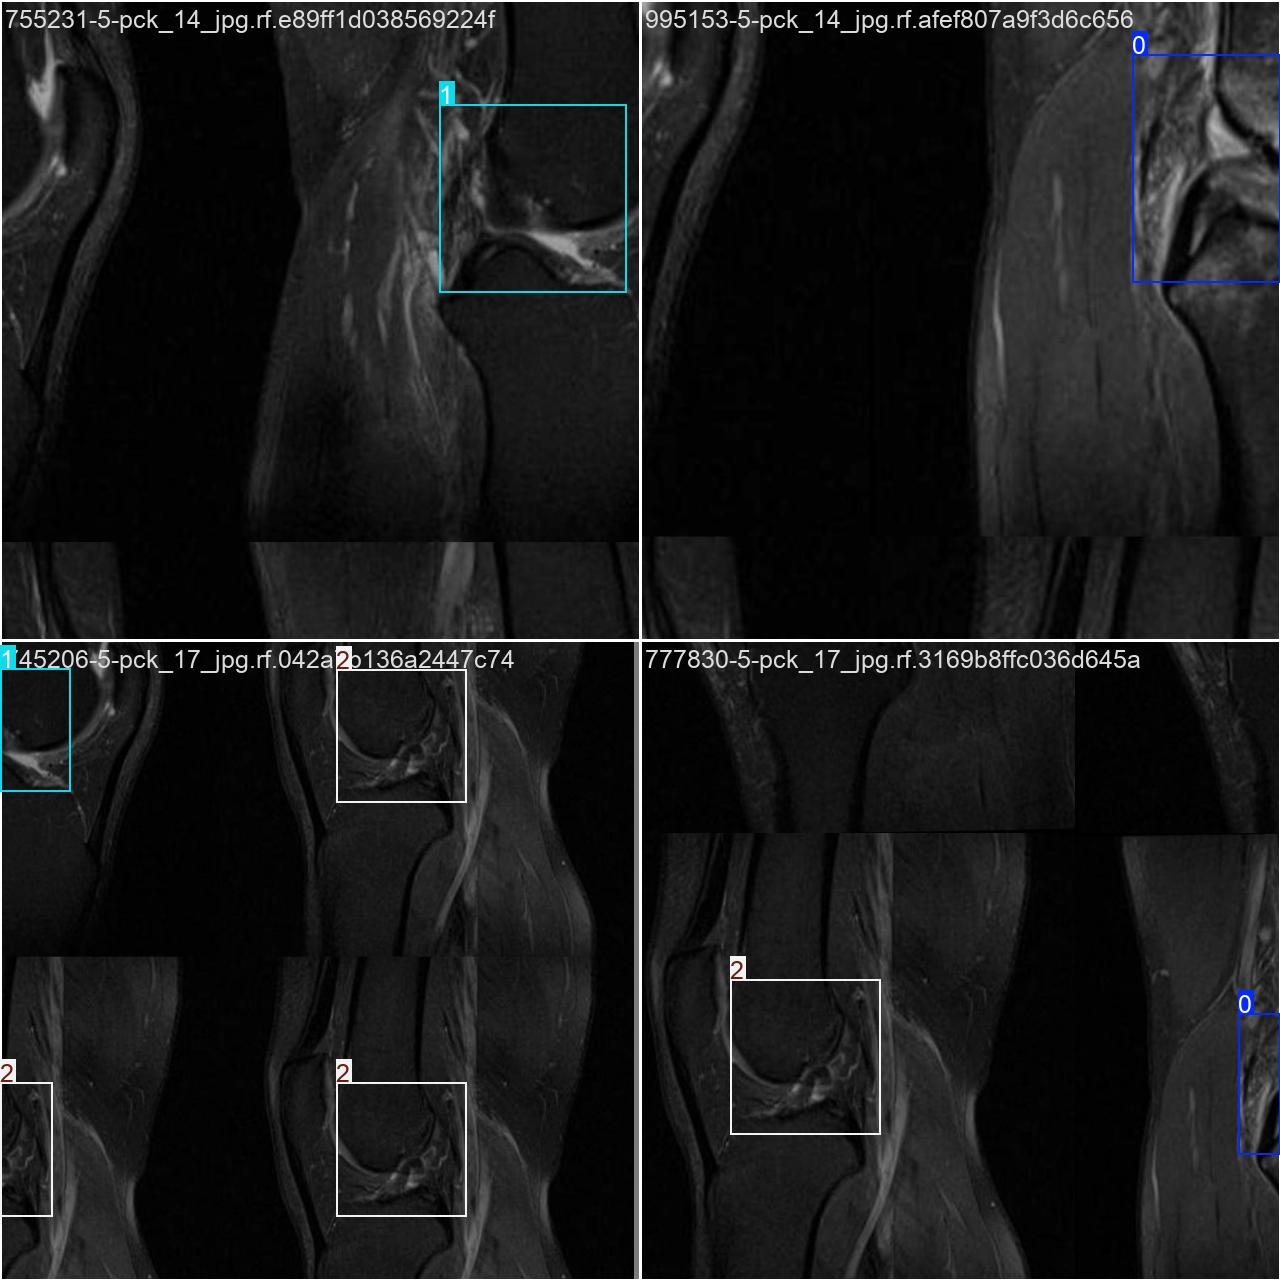

本研究使用了包含膝关节损伤的数据集,并通过Labelimg标注工具对每张图像中的目标边框(Bounding Box)及其类别进行标注。然后主要基于YOLOv8n这种模型进行模型的训练,训练完成后对模型在验证集上的表现进行全面的性能评估及对比分析。模型训练和评估流程基本一致,包括:数据集准备、模型训练、模型评估。本次标注的目标类别为膝关节损伤检测,数据集中共计包含7212张图像,其中训练集占6294张,验证集占612张,测试集占306张。部分图像如下图所示:

部分标注如下图所示: